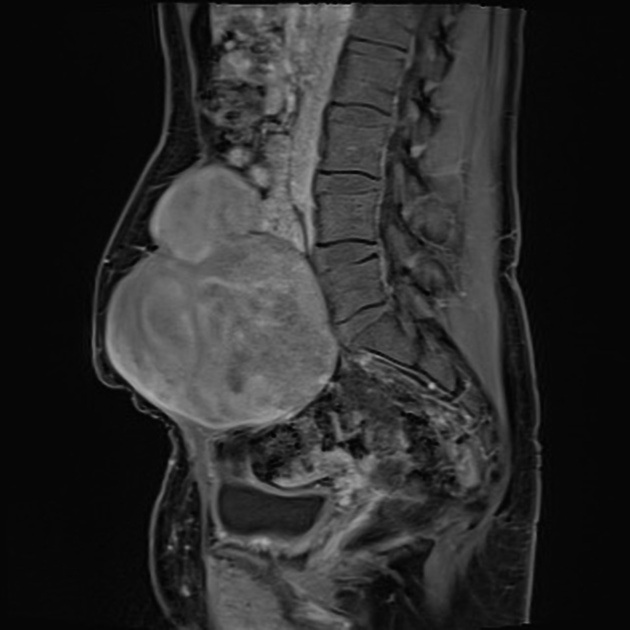

Интраабдоминальная десмоидная опухоль:

- Образование мягкотканной плотности в проекции брыжейки, большого сальника или забрюшинного пространства, с неизменённой архитектурой кишечной стенки.

- Сигнал на Т1 — изоинтенсивный по сравнению с мышцей, с небольшими участками гипоинтенсивности.

- На Т2 — неоднородный гиперинтенсивный сигнал, более выраженный в зонах с клеточной пролиферацией.

- После контрастного усиления выявляется постепенное, неравномерное накопление контраста — центральные зоны усиливаются медленно, периферия — интенсивнее.

- Признаки сдавления или смещения кишки, мочеточника, сосудов без признаков инвазии в полые органы.

- Может наблюдаться деформация брыжеечных сосудов и утрата жировых прослоек между опухолью и прилежащими структурами.

- Нередко визуализируется инфильтрация фасциальных оболочек и жировой клетчатки.